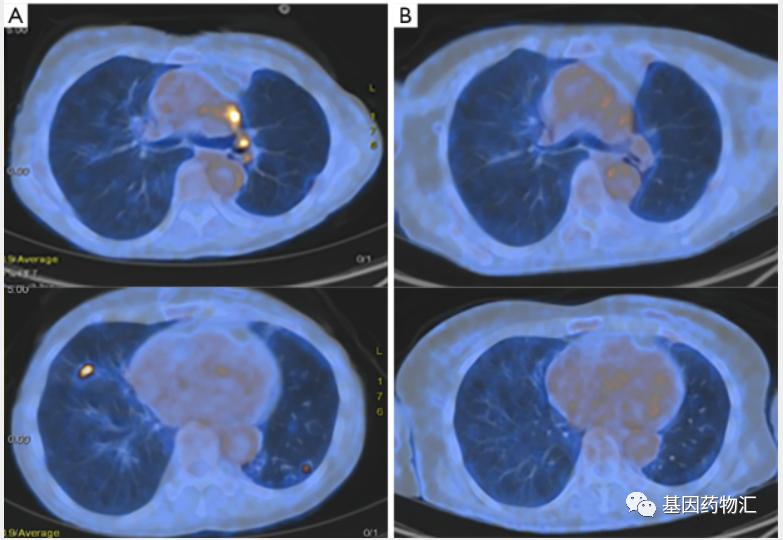

患者从2019年2月开始用药,至2019年5月几乎达到了完全缓解。至2021年5月最后随访时,患者仍然没有任何进展的迹象!

患者从2018年7月开始接受卡铂+培美曲塞治疗,4个周期后继续使用培美曲塞维持治疗1年。至2019年7月患者复查CT时发现肺部和淋巴结进展,于是接受了Amivantamab(JNJ-6372,JNJ-61186372)的治疗,再次达到临床缓解,持续了9个月。